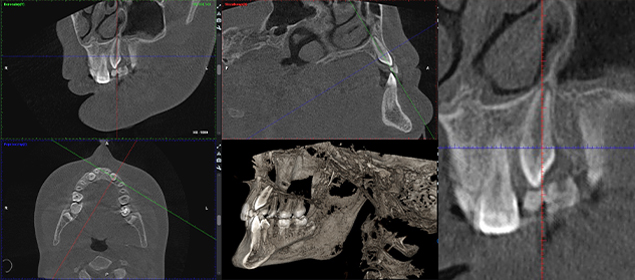

>   Obraz z badania CBCT – szczegóły zębów i wynik analizy / Obraz z badania CBCT – szczegóły zębów i wynik analizy.